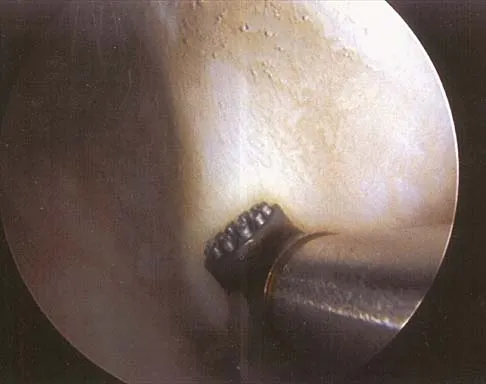

Figure 25 shows an arthroscopic thermal capsular shrinkage device being used in the anterior inferior quadrant of a patient with a subluxating shoulder. Which of the following neurologic complications is most frequently reported with this technique?